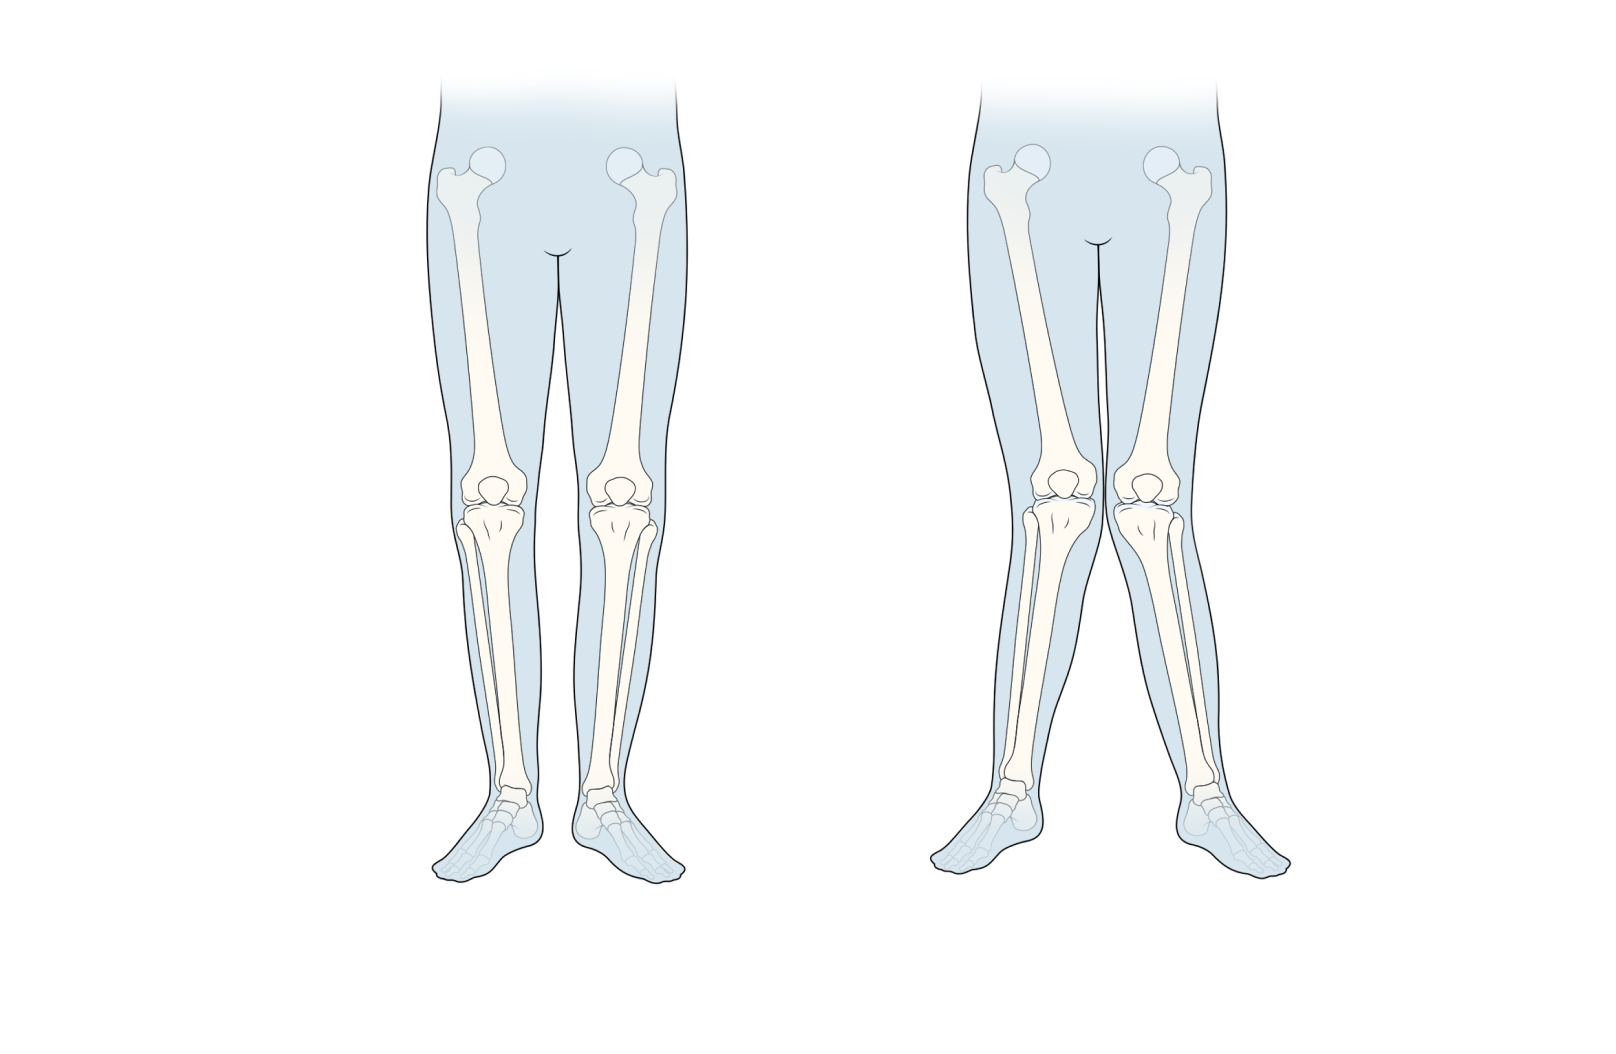

It evaluates various clinical parameters, including reduction in joint space, presence of osteophytes, sclerosis, tibial spikes, bone alignment, and post-operative conditions.

OsteoCheck is a diagnostic system that evaluates bone degeneration, categorizing severity into grades ranging from 1 to 4.